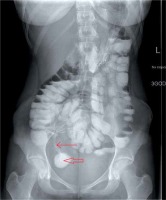

Abdominal X-ray is a low-cost examination, widely used in internal medicine, gastroenterology, and emergency units. Its availability and rapid evaluation of the image are suitable for acute situations like intestinal obstruction, shown as dilated bowel loops with air-fluid levels (Figure 1) or perforation, represented as a free intra-abdominal gas. According to ECCO guidelines, plain film radiography enables detection of small bowel obstruction in stricturing CD. However, the findings from radiography should be followed by further diagnostic study using ultrasonography or other cross-sectional imaging techniques [1]. To exclude a perforation both upright and supine projections should be performed. For patients who cannot maintain a standing position, left lateral decubitus positioning is recommended [2]. Other abnormalities that can be detected by a plain radiography are: toxic megacolon and colonic haustrations loss. Toxic megacolon constitutes a severe complication, more frequent in UC than in CD. It can be diagnosed by an abdominal X-ray as a colonic dilatation larger than 6 cm in the presence of clinical signs of toxicity [3]. In conclusion, the role of plain radiograms in the assessment of IBD can be defined as a first-line examination of acute, life-threatening complications.